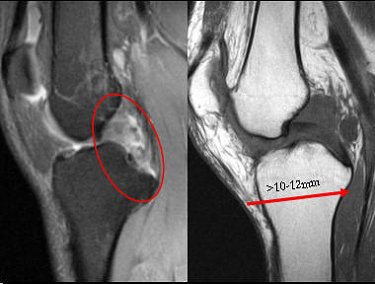

Beall pointed out that PCL reconstruction is an effective treatment method for an injured PCL, but controversy remains over repair versus conservative treatment. Unlike the ACL, even severe PCL injuries have been known to heal fairly quickly. But debate continues over a correlation between the location of the PCL injury and its propensity for healing. A PCL tear may be less likely to heal under the following conditions, Beall said:

- Complete tear of the anteriolateral and posteromedial bundles

- Associated MCL/posterolateral corner injury

- Post-translation greater than 10-12 mm on stress radiography

Presence of any of the above elements will most likely mean surgery, he added. "It really makes it necessary to have a complete MR evaluation so that if you have tears of both bundles that are really destroyed and (there's) not much left of the PCL, then we should think about (surgical) repair," he said.

As for the PCL, "PCL (injuries) will heal even if they are complete," Beall said. "Which tears don't heal? The ones with medial or lateral complex injuries, and tears that are associated with 10-12 mm or more posterior drawer."